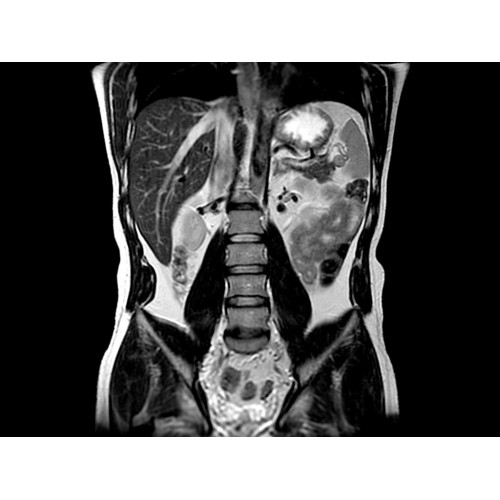

МР-томограф с широким туннелем Optima MR450w является настоящей рабочей лошадкой и может эффективно обслуживать большее число пациентов. Томограф обеспечивает одновременно удобство пациента, продуктивность работы, отличное качество изображения. В этой МРТ-системе инженерам компании удалось без компромиссов совместить необходимый объем перемещения с удивительно высоким качеством изображения.

Благодаря принципиально новым технологиям мы расширили возможности МР-томографов с широкими туннелями, совместив непревзойденное качество изображений с высокой производительностью при широком — 50 см — поле зрения.

• Широкое поле зрения — поле зрения шириной 50 см позволяет охватывать крупные анатомические области за меньшее число сканов.

МР-томограф Optima MR450w с диаметром туннеля 70 см обеспечивает более комфортные условия для пациентов, в первую очередь, для полных людей, детей и лиц, страдающих клаустрофобией. При этом повышенное удобство для пациентов обеспечено не только нешироким туннелем — клинические приложения нового поколения сокращают продолжительность исследований, а улучшенный поток воздуха обеспечивает удобный микроклимат во время исследования.